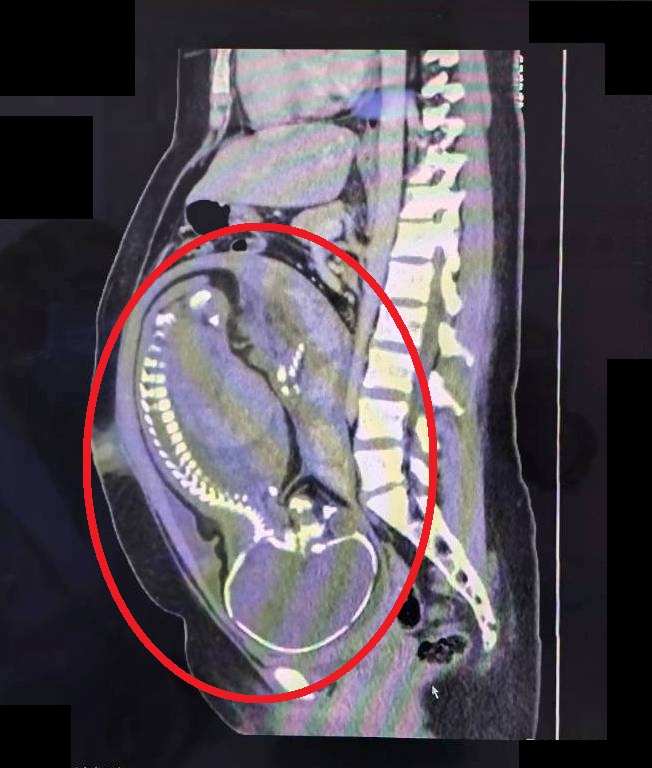

林敬旺醫療副院長表示,該名孕婦懷孕期間產檢一切正常,卻在足月前夕發生持續腹痛,檢查發現白血球數值高達18,360(正常值約4,000-10,000)但體溫正常,且無明顯子宮收縮、子宮頸未擴張、胎心音正常,然而腹部觸診時右下腹有明顯壓痛及反彈痛,因此高度懷疑是急性盲腸炎。當下立即安排腹部電腦斷層(CT)檢查,並會診一般外科劉信誠主任共同評估。經過跨科團隊仔細討論,且與孕婦及家屬充分溝通解釋後,決定執行緊急剖腹生產併盲腸切除手術。

該名孕婦已懷孕39週(紅圈處為腹中寶寶),在跨團隊合作下,順利生產並處理急性盲腸炎問

手術中發現盲腸已嚴重腫脹化膿,瀕臨破裂邊緣,腹腔內更已有約100毫升的膿樣腹水,情況相當危急。所幸,醫療團隊在妥善保護手術傷口避免污染的情況下,順利接生寶寶,同時完成盲腸切除手術。產婦術後接受抗生素治療,恢復良好、順利平安出院。